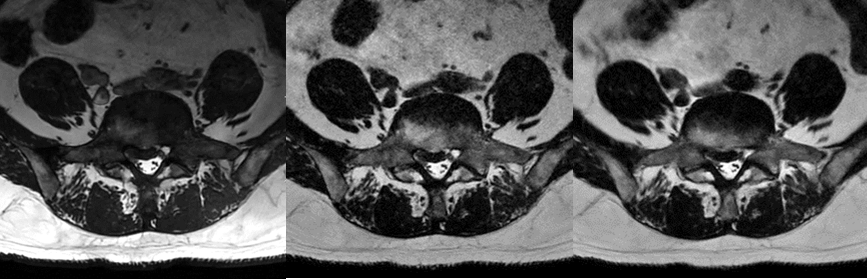

腰椎の検査においてthinsliceによる詳細な評価をする際は、3D FIESTA-Cを追加していたが、 HyperSenseによりCube T2 が扱い易くなり3分程度で撮像可能となった。短時間撮像が可能になった事でルーチンシーケンスに組み込む事ができ、見馴れたT2強調コントラストを提供できる。また、椎間孔に沿った断面と直行断面を撮像すると5分以上要していたが、Cube T2 (HyperSense併用)のボリュームデータからリフォーマットにより対応可能となり、時間短縮に繋がった。(図表3)